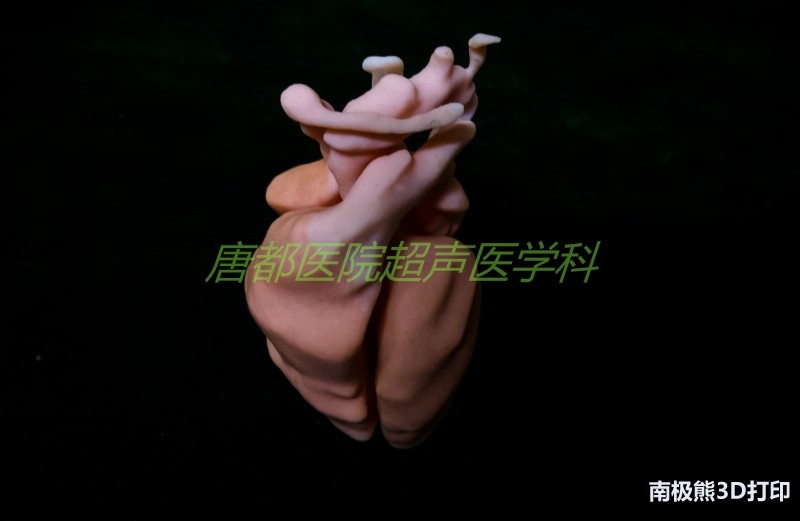

近日,空军军医大学唐都医院超声医学科3D打印研究中心完成了基于超声影像数据的胎儿心脏多色3D打印。该模型完整地呈现了包括胎儿心脏四腔、主动脉弓、降主动脉、动脉导管、肺动脉、上腔静脉、下腔静脉、无名静脉以及卵圆孔、气管和左右主支气管等解剖结构,成功地将胎儿心脏及其周围大动脉、静脉和气管之间的空间结构关系精准还原,最终利用光固化多色打印技术清晰地展现出来。

胎儿心脏模型整体体积相比于实际大小放大了8倍,模型的长宽高分别约为33 mm、25 mm和24 mm。此次三维建模历时3小时,色彩贴图6小时,3D打印及后处理约8-9小时完成。

最后,3D打印的个体化胎儿心脏实体模型区别于传统的教学模具,能够展现出更真实的生理解剖结构,不论是正常的还是异常的胎心模型,都可作为临床教学十分直观的工具。